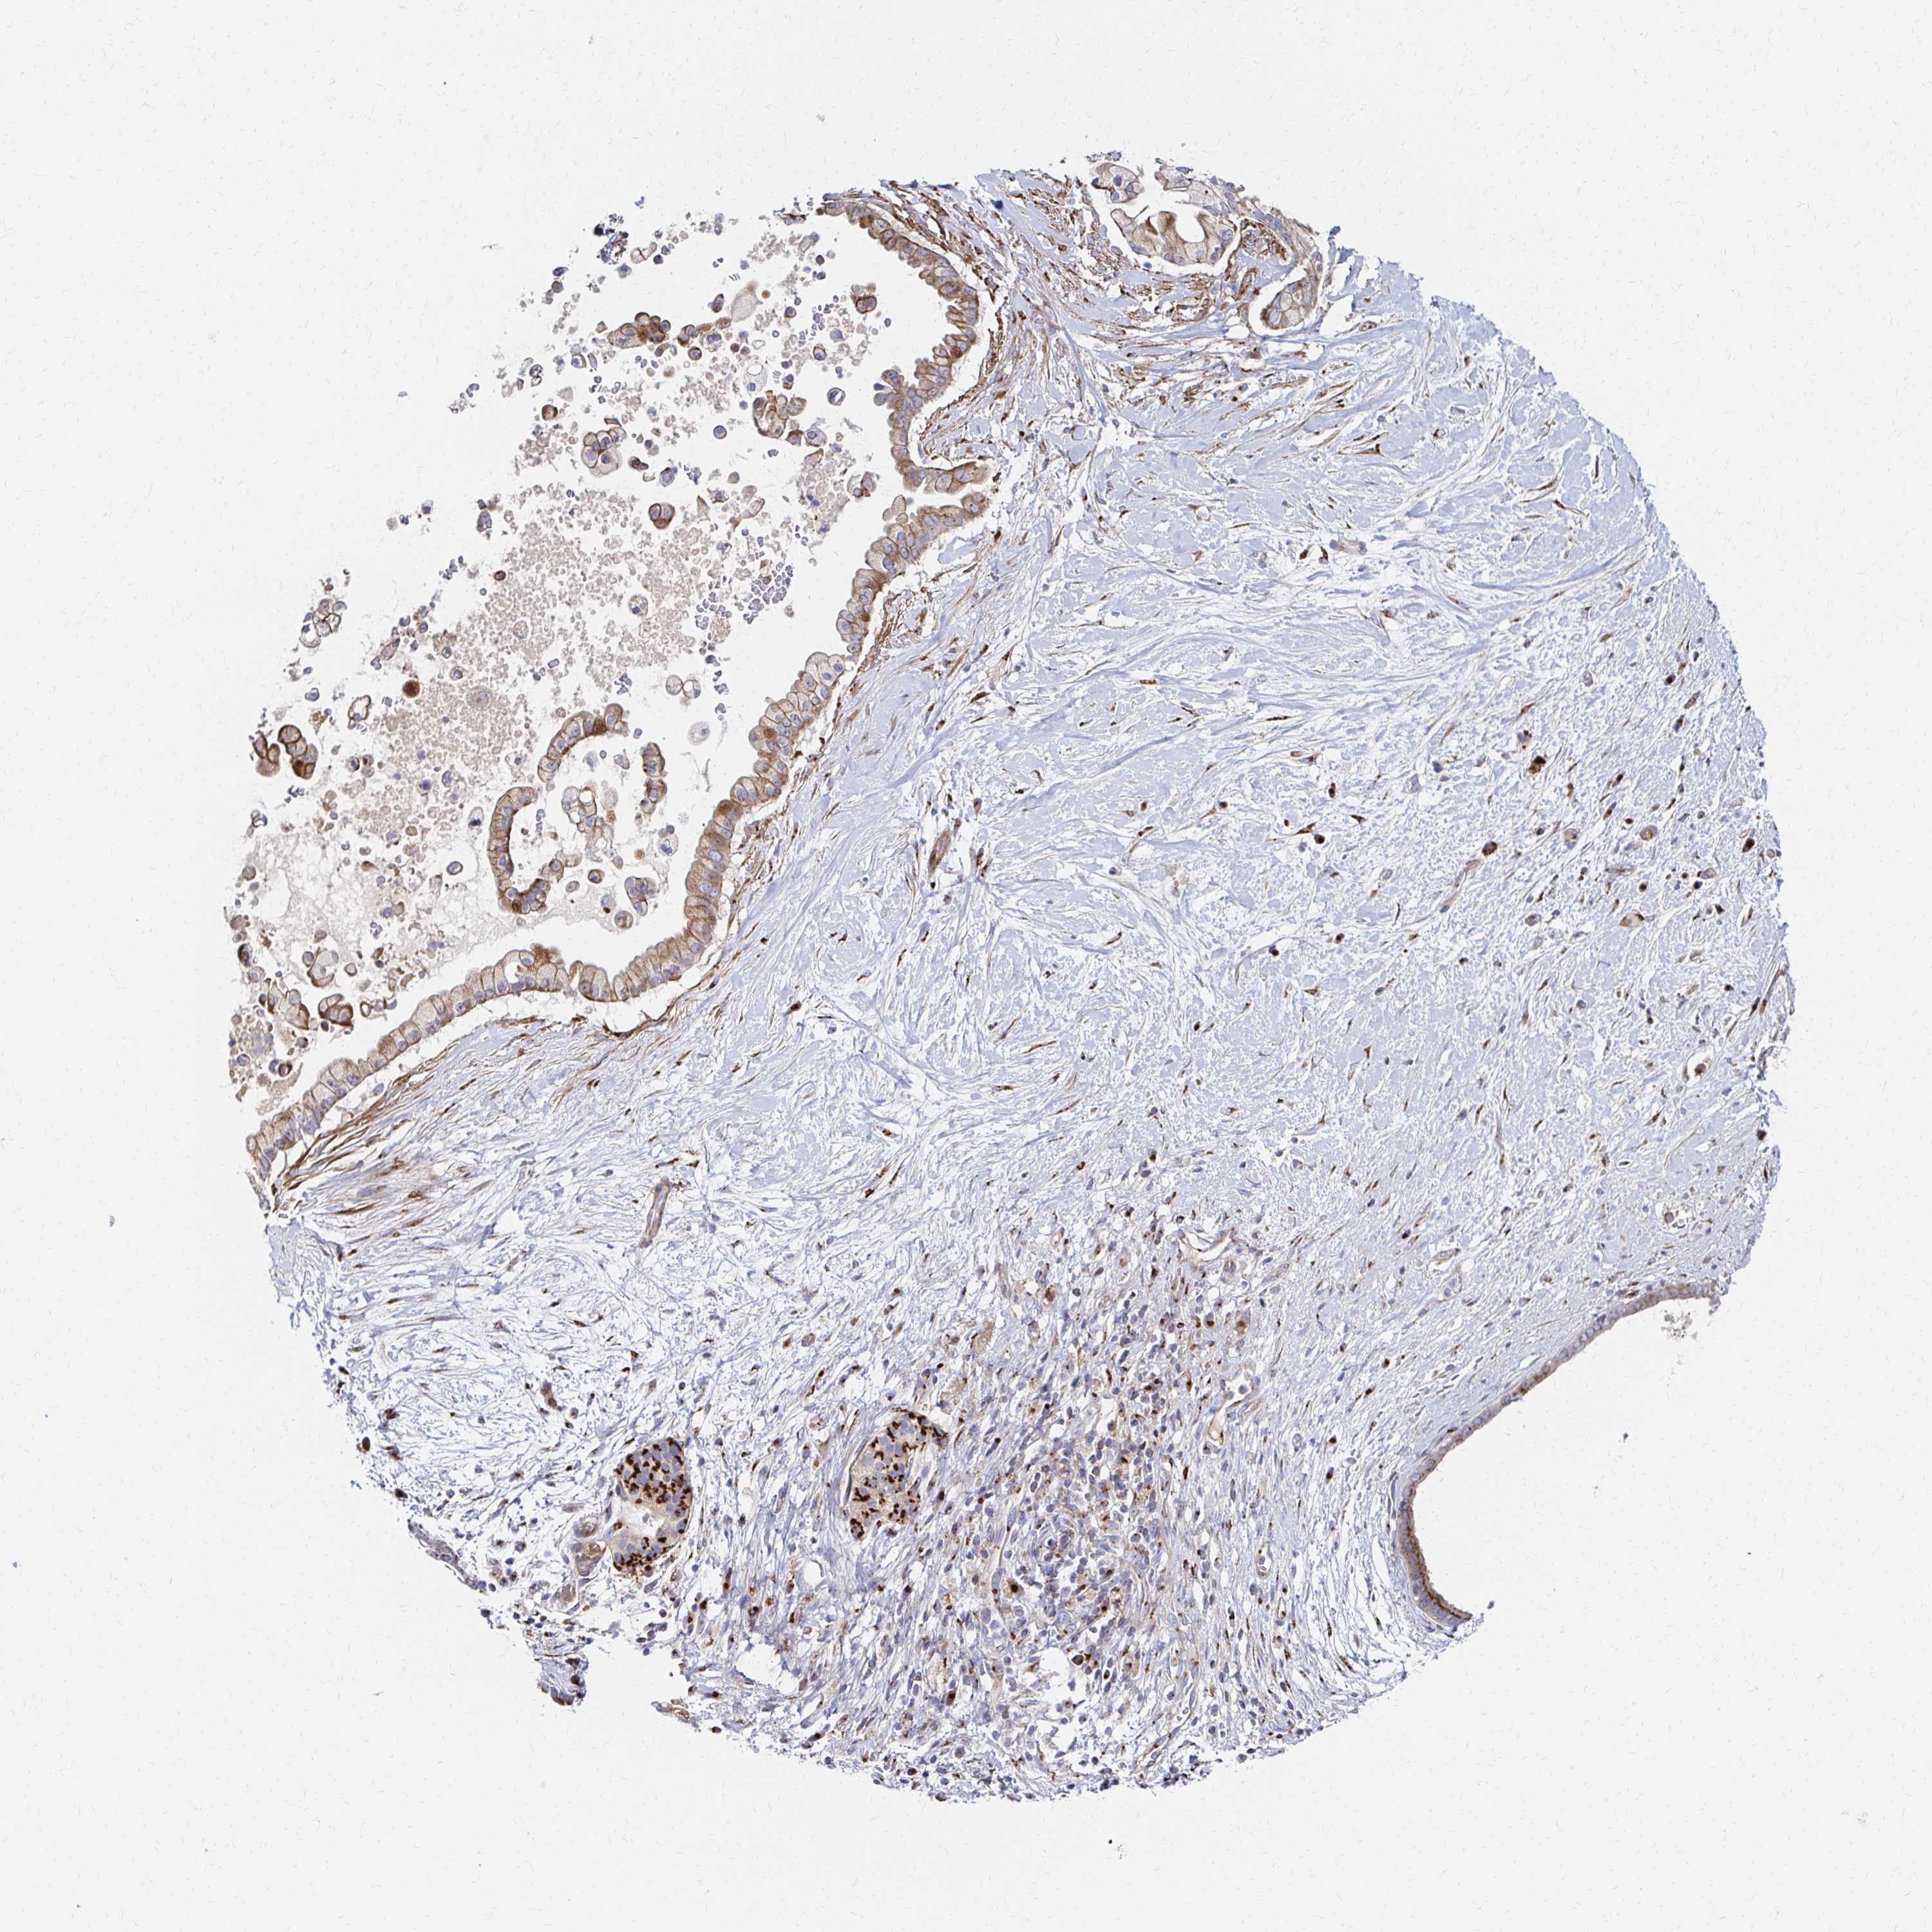

PANCREATIC CANCER - Protein expressioni

A mouse-over function shows sample information and annotation data. Click on an image to view it in a full screen mode. Samples can be filtered based on level of antibody staining by selecting one or several of the following categories: high, medium, low and not detected. The assay and annotation is described here.

Note that samples used for immunohistochemistry by the Human Protein Atlas do not correspond to samples in the TCGA dataset.

Antibody stainingi

Antibody staining in the annotated cell types in the current human tissue is reported as not detected, low, medium, or high, based on conventional immunohistochemistry profiling in selected tissues. This score is based on the combination of the staining intensity and fraction of stained cells.

Each image is clickable and will lead to virtual microscopy that enables deeper exploration of all samples and also displays staining intensity scores, fraction scores and subcellular localization as well as patient and tissue information for each sample.

Antibody HPA053198

Antibody HPA063561

Antibody CAB037058

Staining

High

Medium

Low

Not detected

Intensity

Strong

Moderate

Weak

Negative

Quantity

>75%

75%-25%

<25%

None

Location

Nuclear

Cytoplasmic/membranous

Cytoplasmic/membranous,nuclear

Adenocarcinoma, NOS